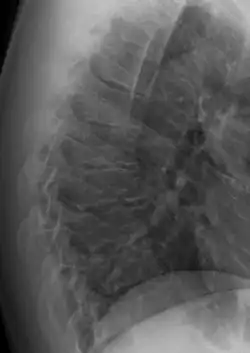

| Scheuermann's disease on lateral Xray of the T spine | |